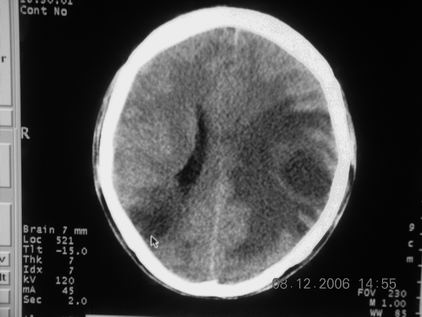

标题: CT11164:男,46岁,白血病患者,,大家看看. [打印本页]

标题: CT11164:男,46岁,白血病患者,,大家看看.

以前的片子,病史忘了,男,46岁,白血病患者,后来到中山二院诊断为

谁见过白血病中枢系统改变是怎么样的吗?

白血病脑浸润。

支持白血病脑浸润.

1 多发脑脓肿可能性大.>2 白血病浸润.

白血病脑浸润。没见过!但结合病史应首先考虑此病。

支持白血病脑浸润

结合病史考虑白血病脑浸润。

结合白血病病史,支持考虑白血病脑浸润。

结合病史考虑白血病脑浸润